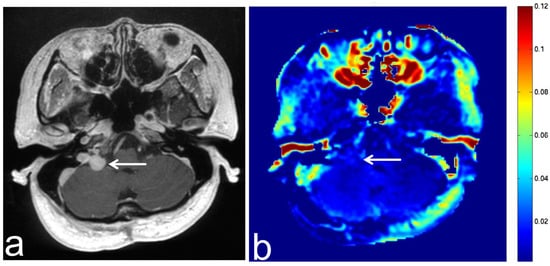

7.3. Schwannoma